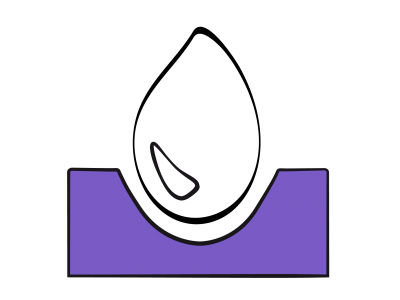

La fonction diastolique représente la capacité du ventricule à accommoder un remplissage adéquat sous un régime de pression basse et sur un vaste éventail de conditions de charge (voir Chapitre 5 La diastole). La dysfonction diastolique se réfère à une anomalie des indices échocardiographiques du remplissage ventriculaire qui reste cliniquement asymptomatique sauf à l'effort majeur, alors que l’insuffisance diastolique, responsable de près de 50% des insuffisances cardiaques congestives, est un syndrome clinique qui se caractérise par une dyspnée et une élévation chronique des pressions de remplissage (POG > 16 mmHg) en présence d’une fonction systolique préservée (FE > 0.5) [2,4]. Dans tous les cas, la pression télédiastolique ventriculaire est plus haute pour un même volume de précharge [2,7]. Une dysfonction diastolique est toujours présente en cas d’insuffisance ventriculaire systolique.

La fonction diastolique représente la capacité du ventricule à accommoder un remplissage adéquat sous un régime de pression basse et sur un vaste éventail de conditions de charge (voir Chapitre 5 La diastole). La dysfonction diastolique se réfère à une anomalie des indices échocardiographiques du remplissage ventriculaire qui reste cliniquement asymptomatique sauf à l'effort majeur, alors que l’insuffisance diastolique, responsable de près de 50% des insuffisances cardiaques congestives, est un syndrome clinique qui se caractérise par une dyspnée et une élévation chronique des pressions de remplissage (POG > 16 mmHg) en présence d’une fonction systolique préservée (FE > 0.5) [2,4]. Dans tous les cas, la pression télédiastolique ventriculaire est plus haute pour un même volume de précharge [2,7]. Une dysfonction diastolique est toujours présente en cas d’insuffisance ventriculaire systolique.